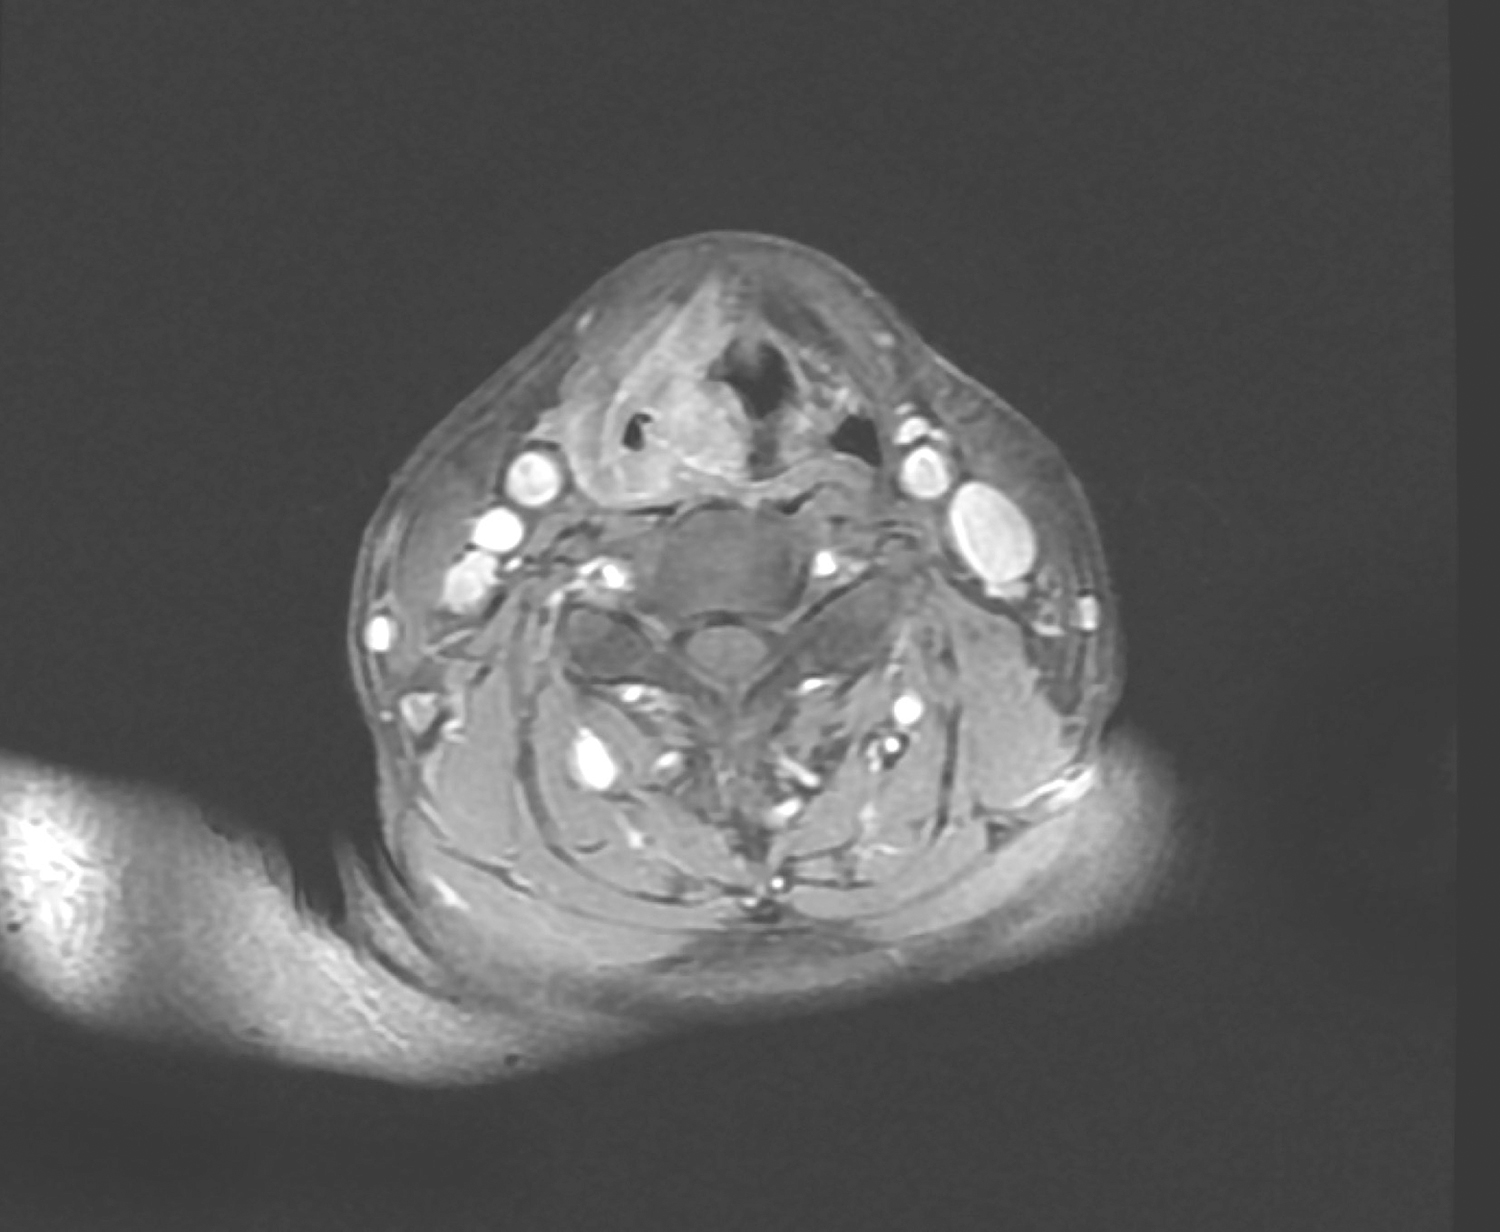

1小时条评论31岁女性,查体发现癌胚抗原升高2年,发现甲状腺肿物2个月余,临床符合甲状腺髓样癌,如何治疗? 【病例简介】 患者女性,31岁。因查体发现癌胚抗原升高2年,发现甲状腺肿物2个月余,于2018年3月5日收入本院头颈外科。2年前查体发现癌胚抗原升高,数值逐渐增...